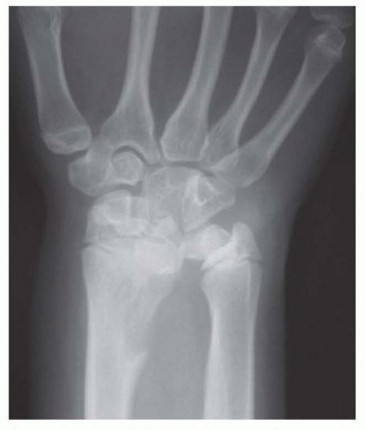

Imaging serves as our architectural blueprint for surgical planning. We mandate a comprehensive plain radiographic series. This begins with strictly neutral rotation posteroanterior (PA) and lateral views of both wrists to accurately assess static ulnar variance and the morphology of the sigmoid notch. However, static views are insufficient. We must obtain a pronated grip view (the clenched fist PA). As Tomaino and others have definitively demonstrated, active power grip forces the radius proximally relative to the ulna, increasing dynamic ulnar variance by an average of 2.5 mm. This view often unmasks profound dynamic impaction in wrists that appear neutrally variant on resting films.

Meticulous pre-operative planning is the difference between a masterfully executed surgery and an intraoperative struggle. The process begins with precise radiographic templating. Using calibrated PA and clenched fist radiographs, we calculate the exact millimeter resection required to achieve our goal: a neutral to slightly negative (-1 mm) ulnar variance. We must account for the thickness of the saw blade (kerf), which typically removes an additional 1 mm of bone. Over-shortening is a critical error; resecting more than 5 to 6 mm can drastically alter the kinematics of the DRUJ, potentially leading to impingement of the ulnar head against the proximal margin of the sigmoid notch.